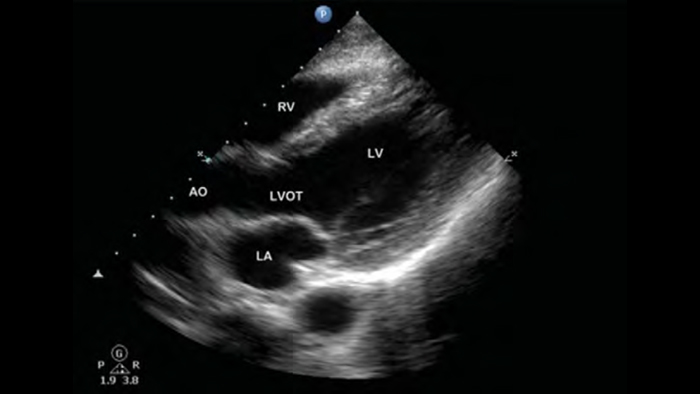

A patient with dyspnea (Ein Patient mit Dyspnoe)

Tutorial (Engl.)

Pre-hospital point of care cardiac ultrasound: pulmonary embolism (Präklinischer Point-of-Care-Ultraschall des Herzens: Lungenembolie)